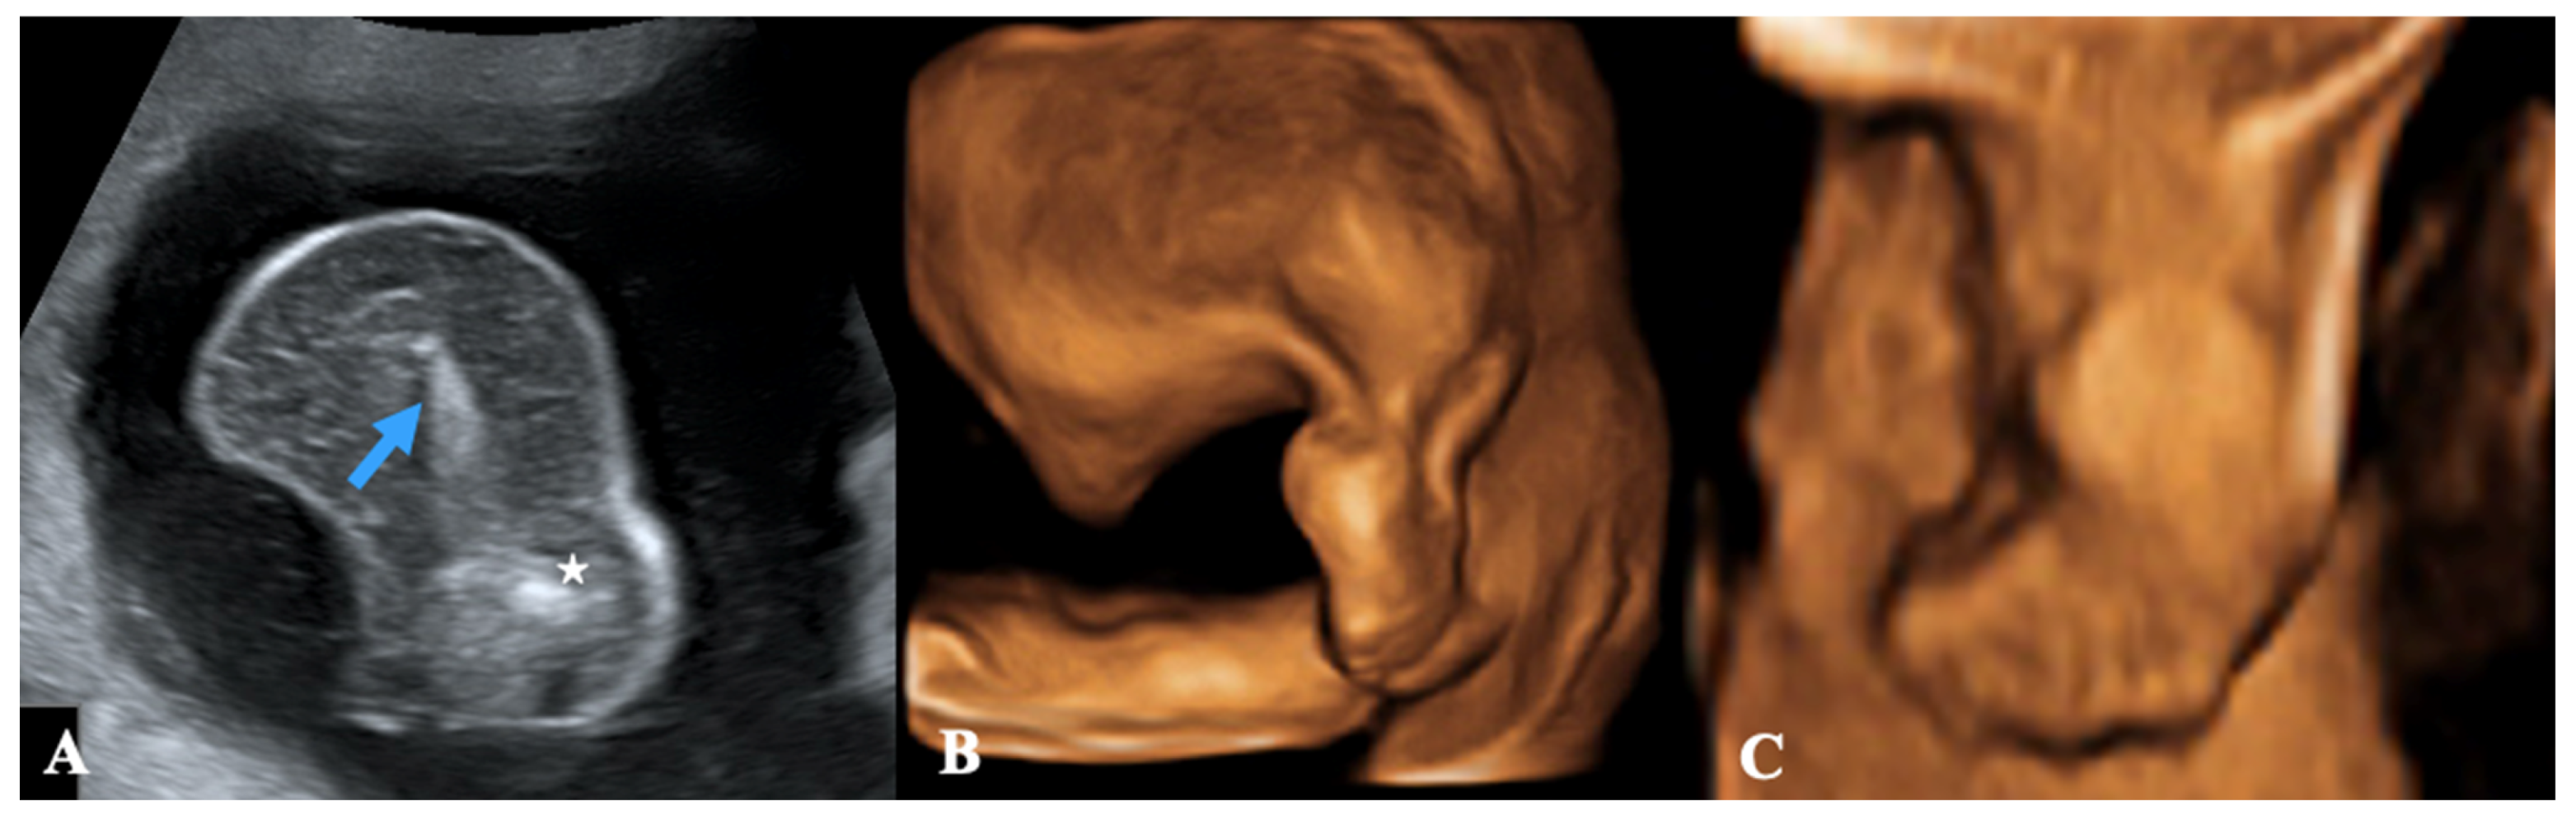

- The most common subtype is the Acardius acephalus, in which the pelvis and lower limbs are well developed, the head and thoracic organs are missing, and poorly developed upper extremities may be present or absent.

- The Acardius anceps is the most developed subtype, since both the upper and lower extremities are present and typically well-formed, and head and face are present too, although poorly formed.

- The Acardius amorphus is the least developed subtype, a shapeless mass without differentiable organs, extremities, or anatomic structures.

- The Acardius acormus is an extremely rare subtype; here, the head is the only recognizable organ.